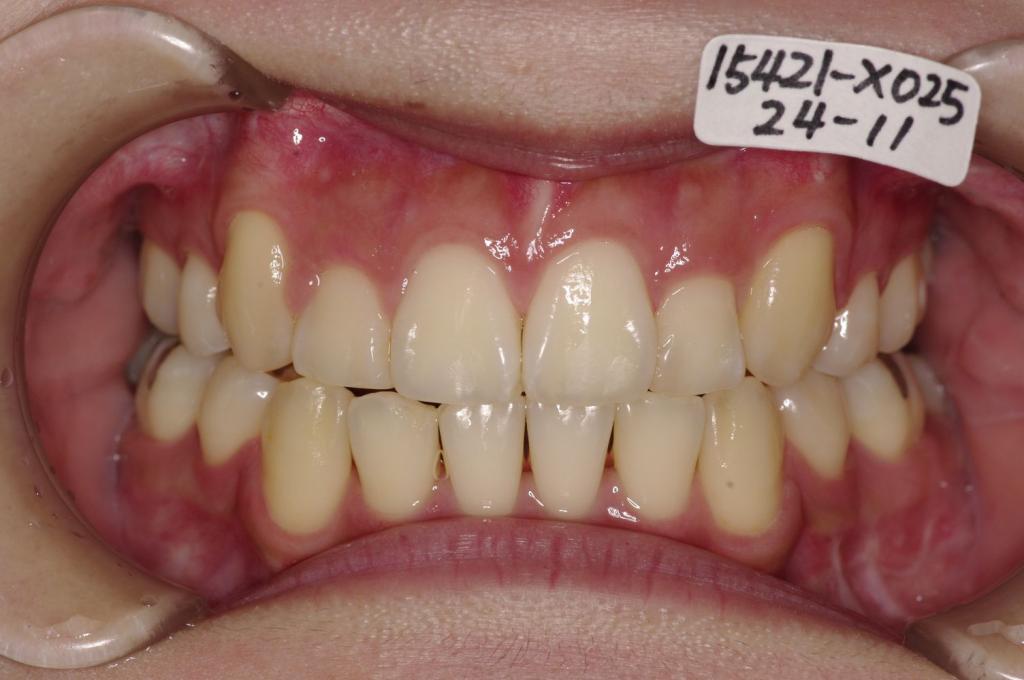

顎、顔の歪みの矯正治療

(治療期間、治療前後写真、治療方法、費用)WORKS